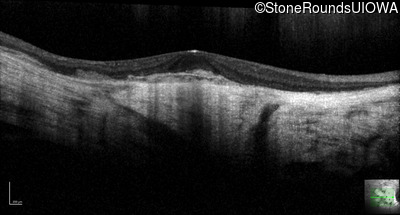

Optical Coherence Tomography - Right - 5/350

Exemplar / OCT Stack